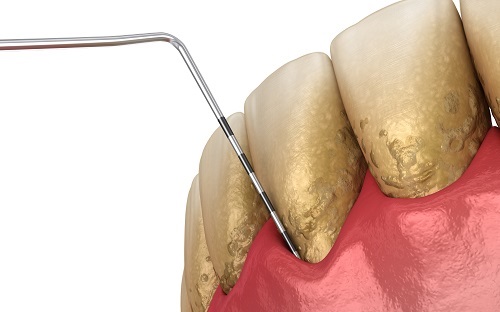

What is Periodontal Disease?

Periodontal disease means bone loss around the teeth. This is different from gingivitis which means inflamed, swollen and possibly bleeding gums but does not, by definition, involve any loss of bone. Both gingivitis and periodontal disease are caused by the bacteria that live in our mouth and grow...  Read More